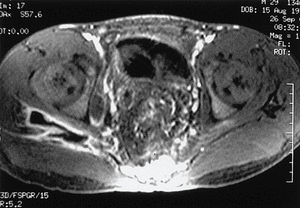

Figura 1. Resonancia magnética de pelvis donde se aprecia la fístula perirrectal.

Figura 2. Tomografía computarizada de pelvis donde se aprecia el absceso presacro y glúteo.

En la RM se observó una fístula perirrectal con colección a espacio presacro y extensión a través de ambas escotaduras ciáticas de predominio derecho hasta la zona posterior de la cadera. Asimismo, había una fístula perianal derecha. En la TC abdominal se confirmó la existencia del absceso presacro con extensión al glúteo medio derecho.